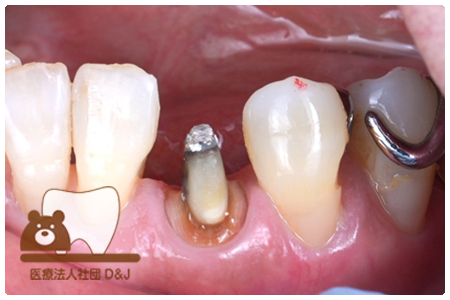

症例3フリジルコニアクラウン 左上6

治療前

治療後

59歳 男性

- 治療内容

- 虫歯で大きく失われた歯に対して、土台としてファイバーコアを使用し、その上にフルジルコニア製の被せ物を装着しました。見た目と強度を両立した自由診療の治療です。

- 治療期間

- 根の治療含めて3カ月半

- 費用

- 自費

フリジルコニアクラウン:77,000円(税込)

(R8.2月時点)

- その他の治療の費用は含まれておりません。

- リスク・副作用

- 強い力が加わると割れる可能性があります。また、噛み合わせや歯ぎしりの影響で脱離することがあります。